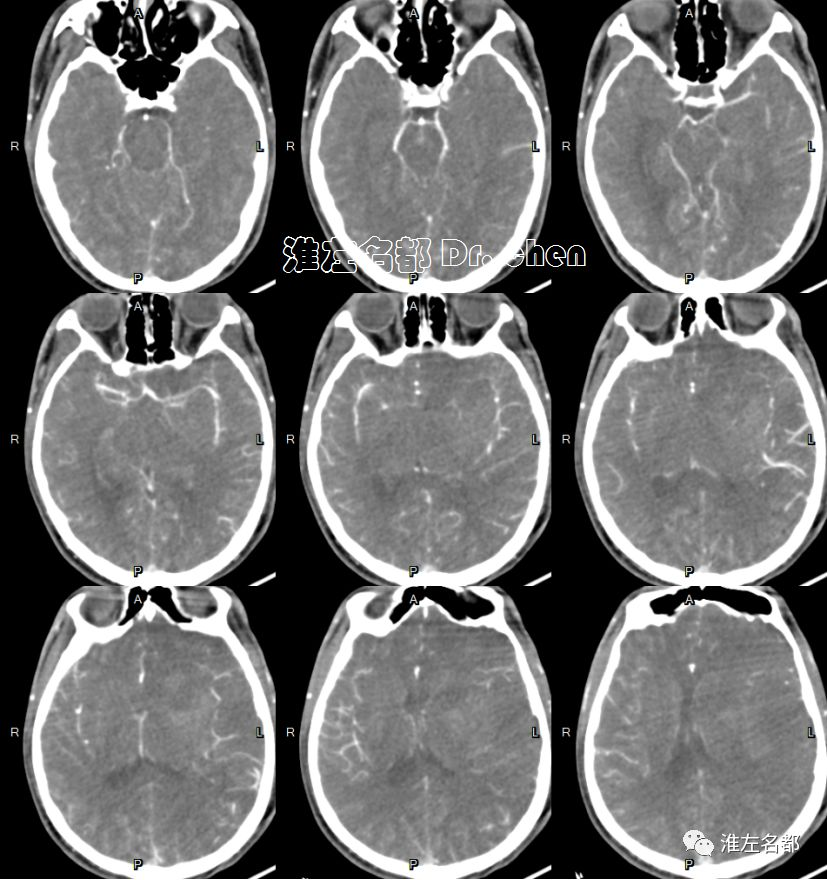

急诊多模式CT

△头颅CTA:左侧颈内动脉末端和大脑中动脉未见显影;左侧颈内动脉显影较右侧细小,造影剂浓度淡(提示血流缓慢)。

△颈部CTA:颈部动脉未见异常。

△脑CTP:左侧半球大范围TTP较对侧显著延长,左侧大脑中动脉上干供血区CBV和CBF显著降低。

△脑CTP静脉早期多平面重建:左侧大脑中动脉主干显影细小(红箭)

复查多模式CT

△头颅CTA:左侧前循环管腔通畅,未见明显狭窄。

△脑CTP:左侧额叶CBV和CBF仍然较对侧显著降低(无复流)